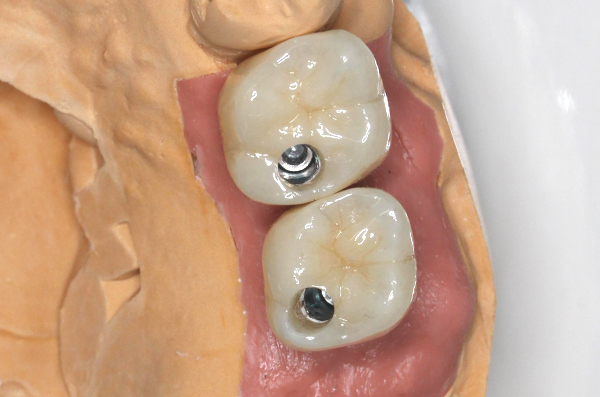

左上67欠損

左上67にインプラント埋入し、ジルコニアにて被せ物を作製した。

検査 4万円 手術/上部構造 34万円×2本 ソケットリフト5万円×1本(税別)

- 喫煙者の方は、インプラント周囲炎やインプラント脱離のリスクが高まります。

- 当院ではナイトガードを使用していただいています。

- 骨幅が足りない、神経までの距離が短いケースは手術を行えないこともあります。